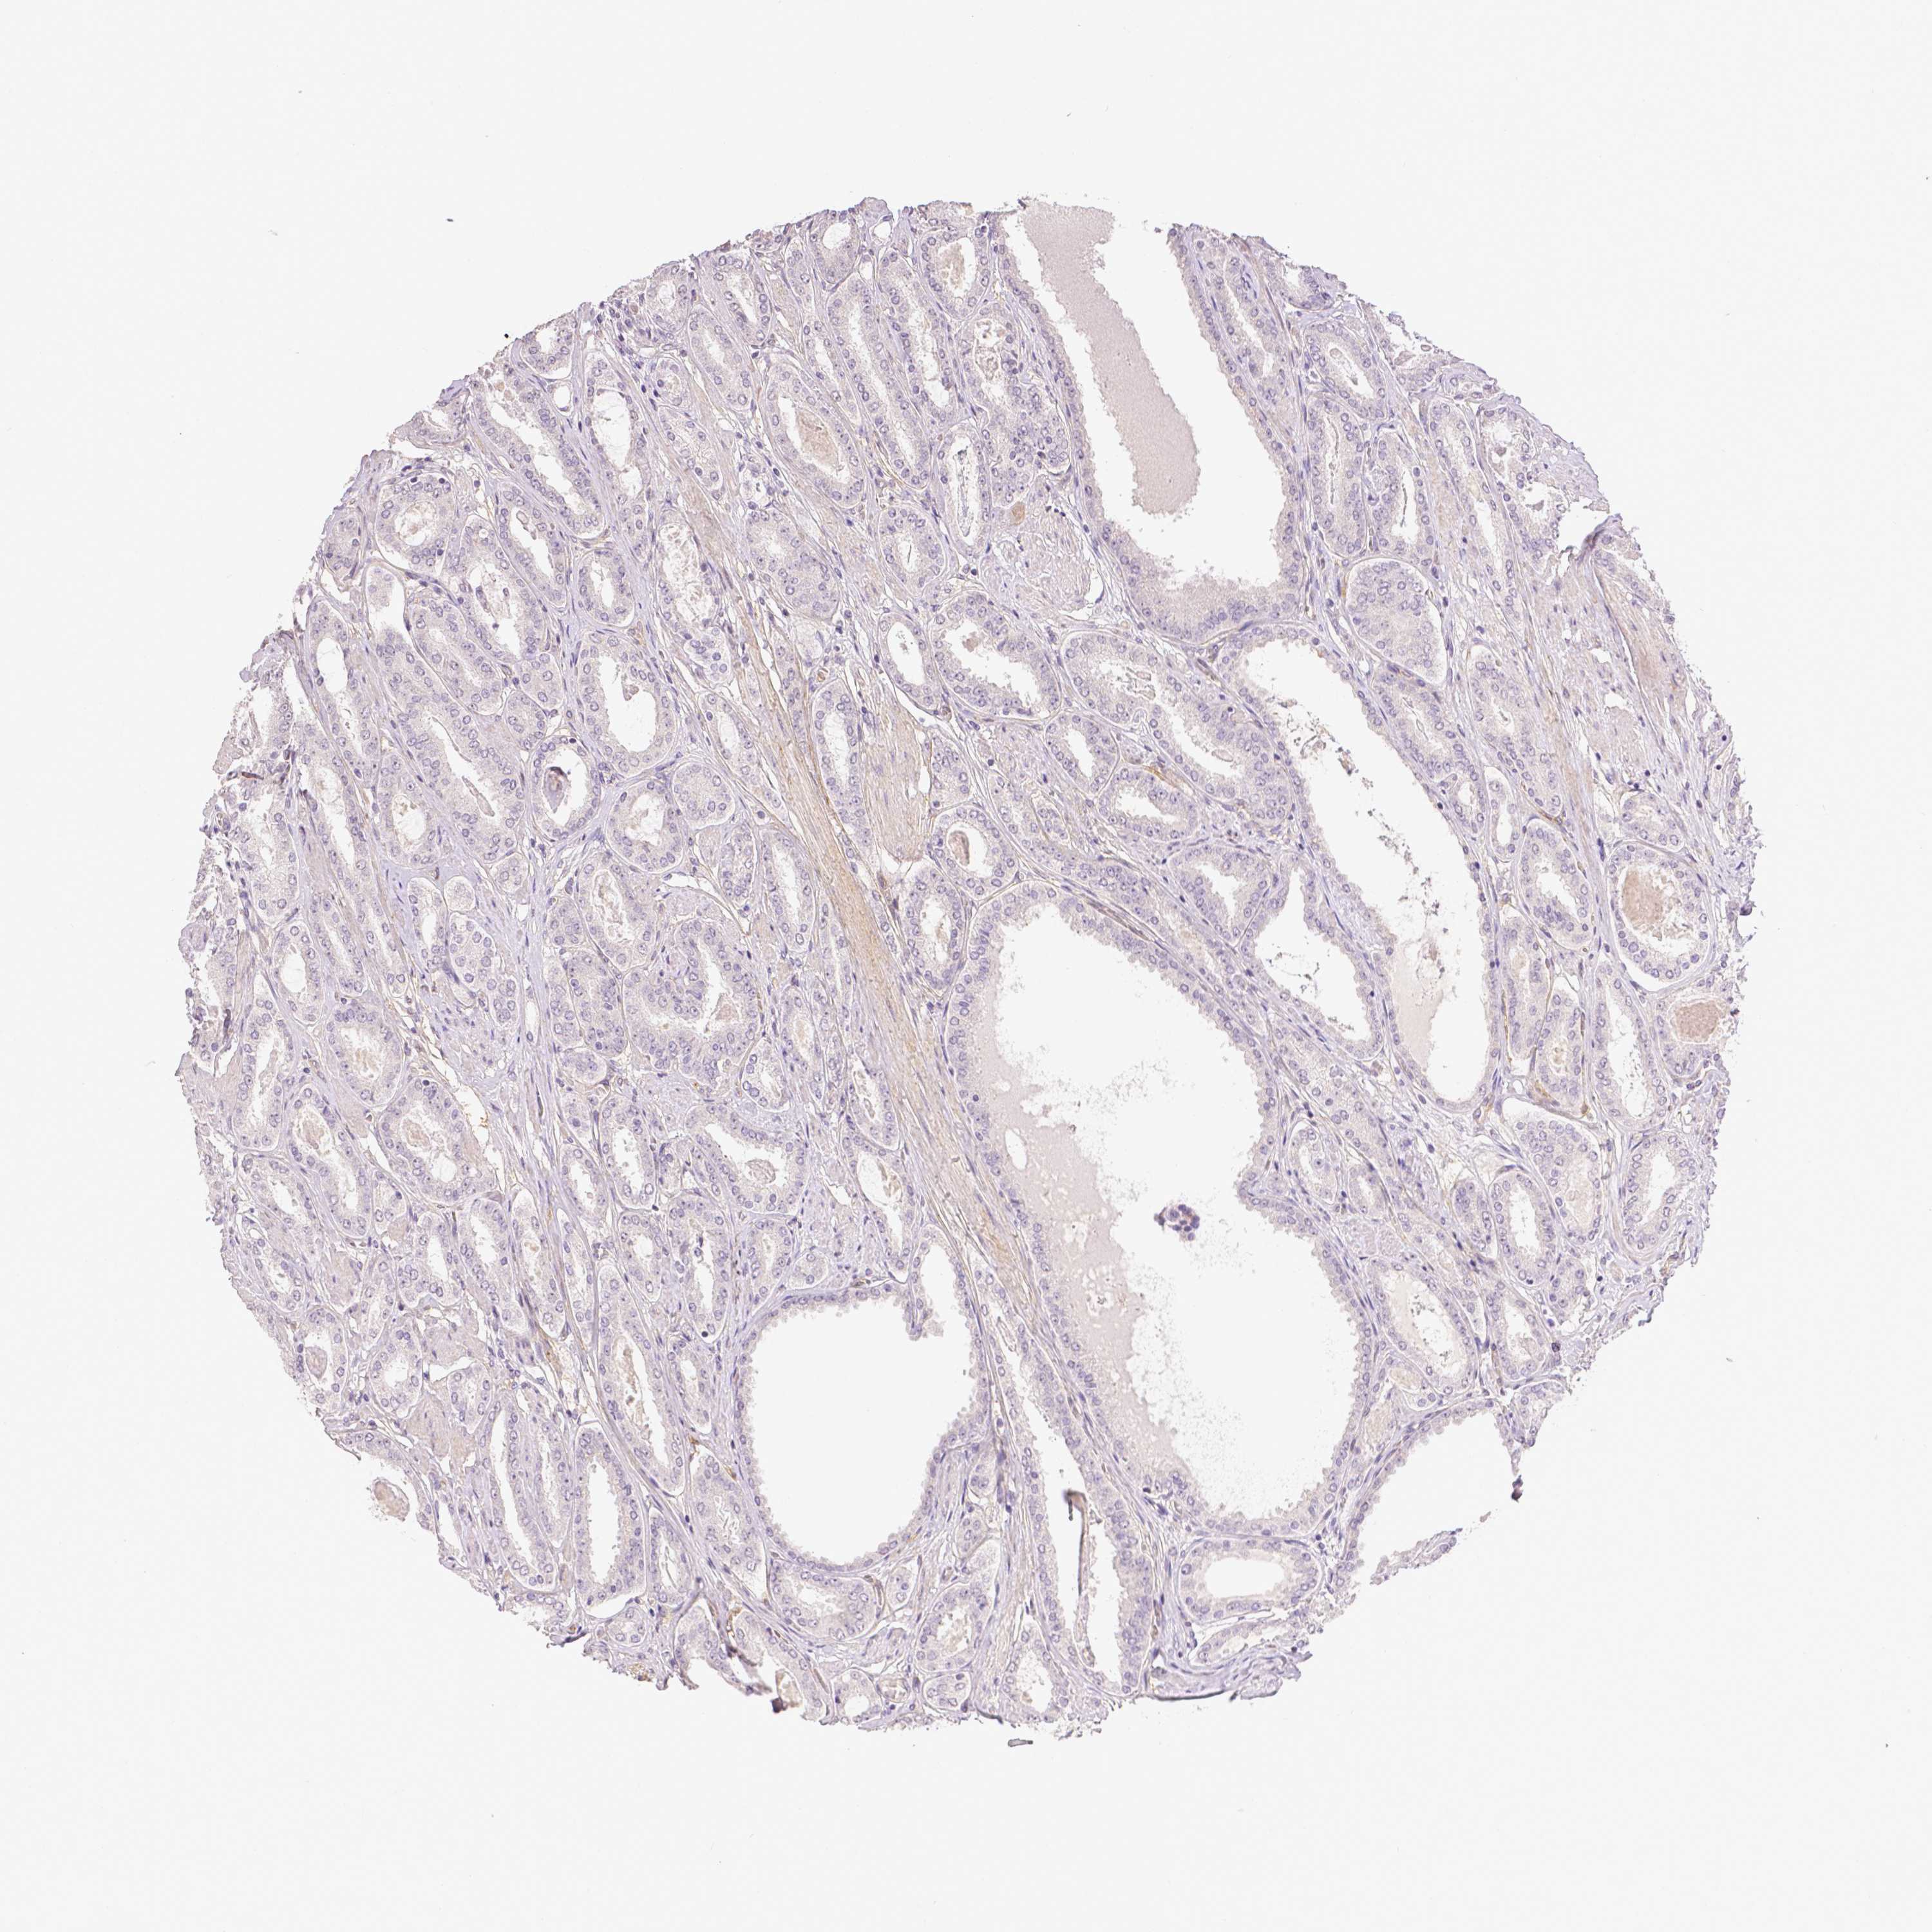

PROSTATE CANCER - Protein expressioni

A mouse-over function shows sample information and annotation data. Click on an image to view it in a full screen mode. Samples can be filtered based on level of antibody staining by selecting one or several of the following categories: high, medium, low and not detected. The assay and annotation is described here.

Antibody stainingi

Antibody staining in the annotated cell types in the current human tissue is reported as not detected, low, medium, or high, based on conventional immunohistochemistry profiling in selected tissues. This score is based on the combination of the staining intensity and fraction of stained cells.

Each image is clickable and will lead to virtual microscopy that enables deeper exploration of all samples and also displays staining intensity scores, fraction scores and subcellular localization as well as patient and tissue information for each sample.

Antibody CAB068244

Adenocarcinoma, High grade

Adenocarcinoma, NOS

Adenocarcinoma, Low grade